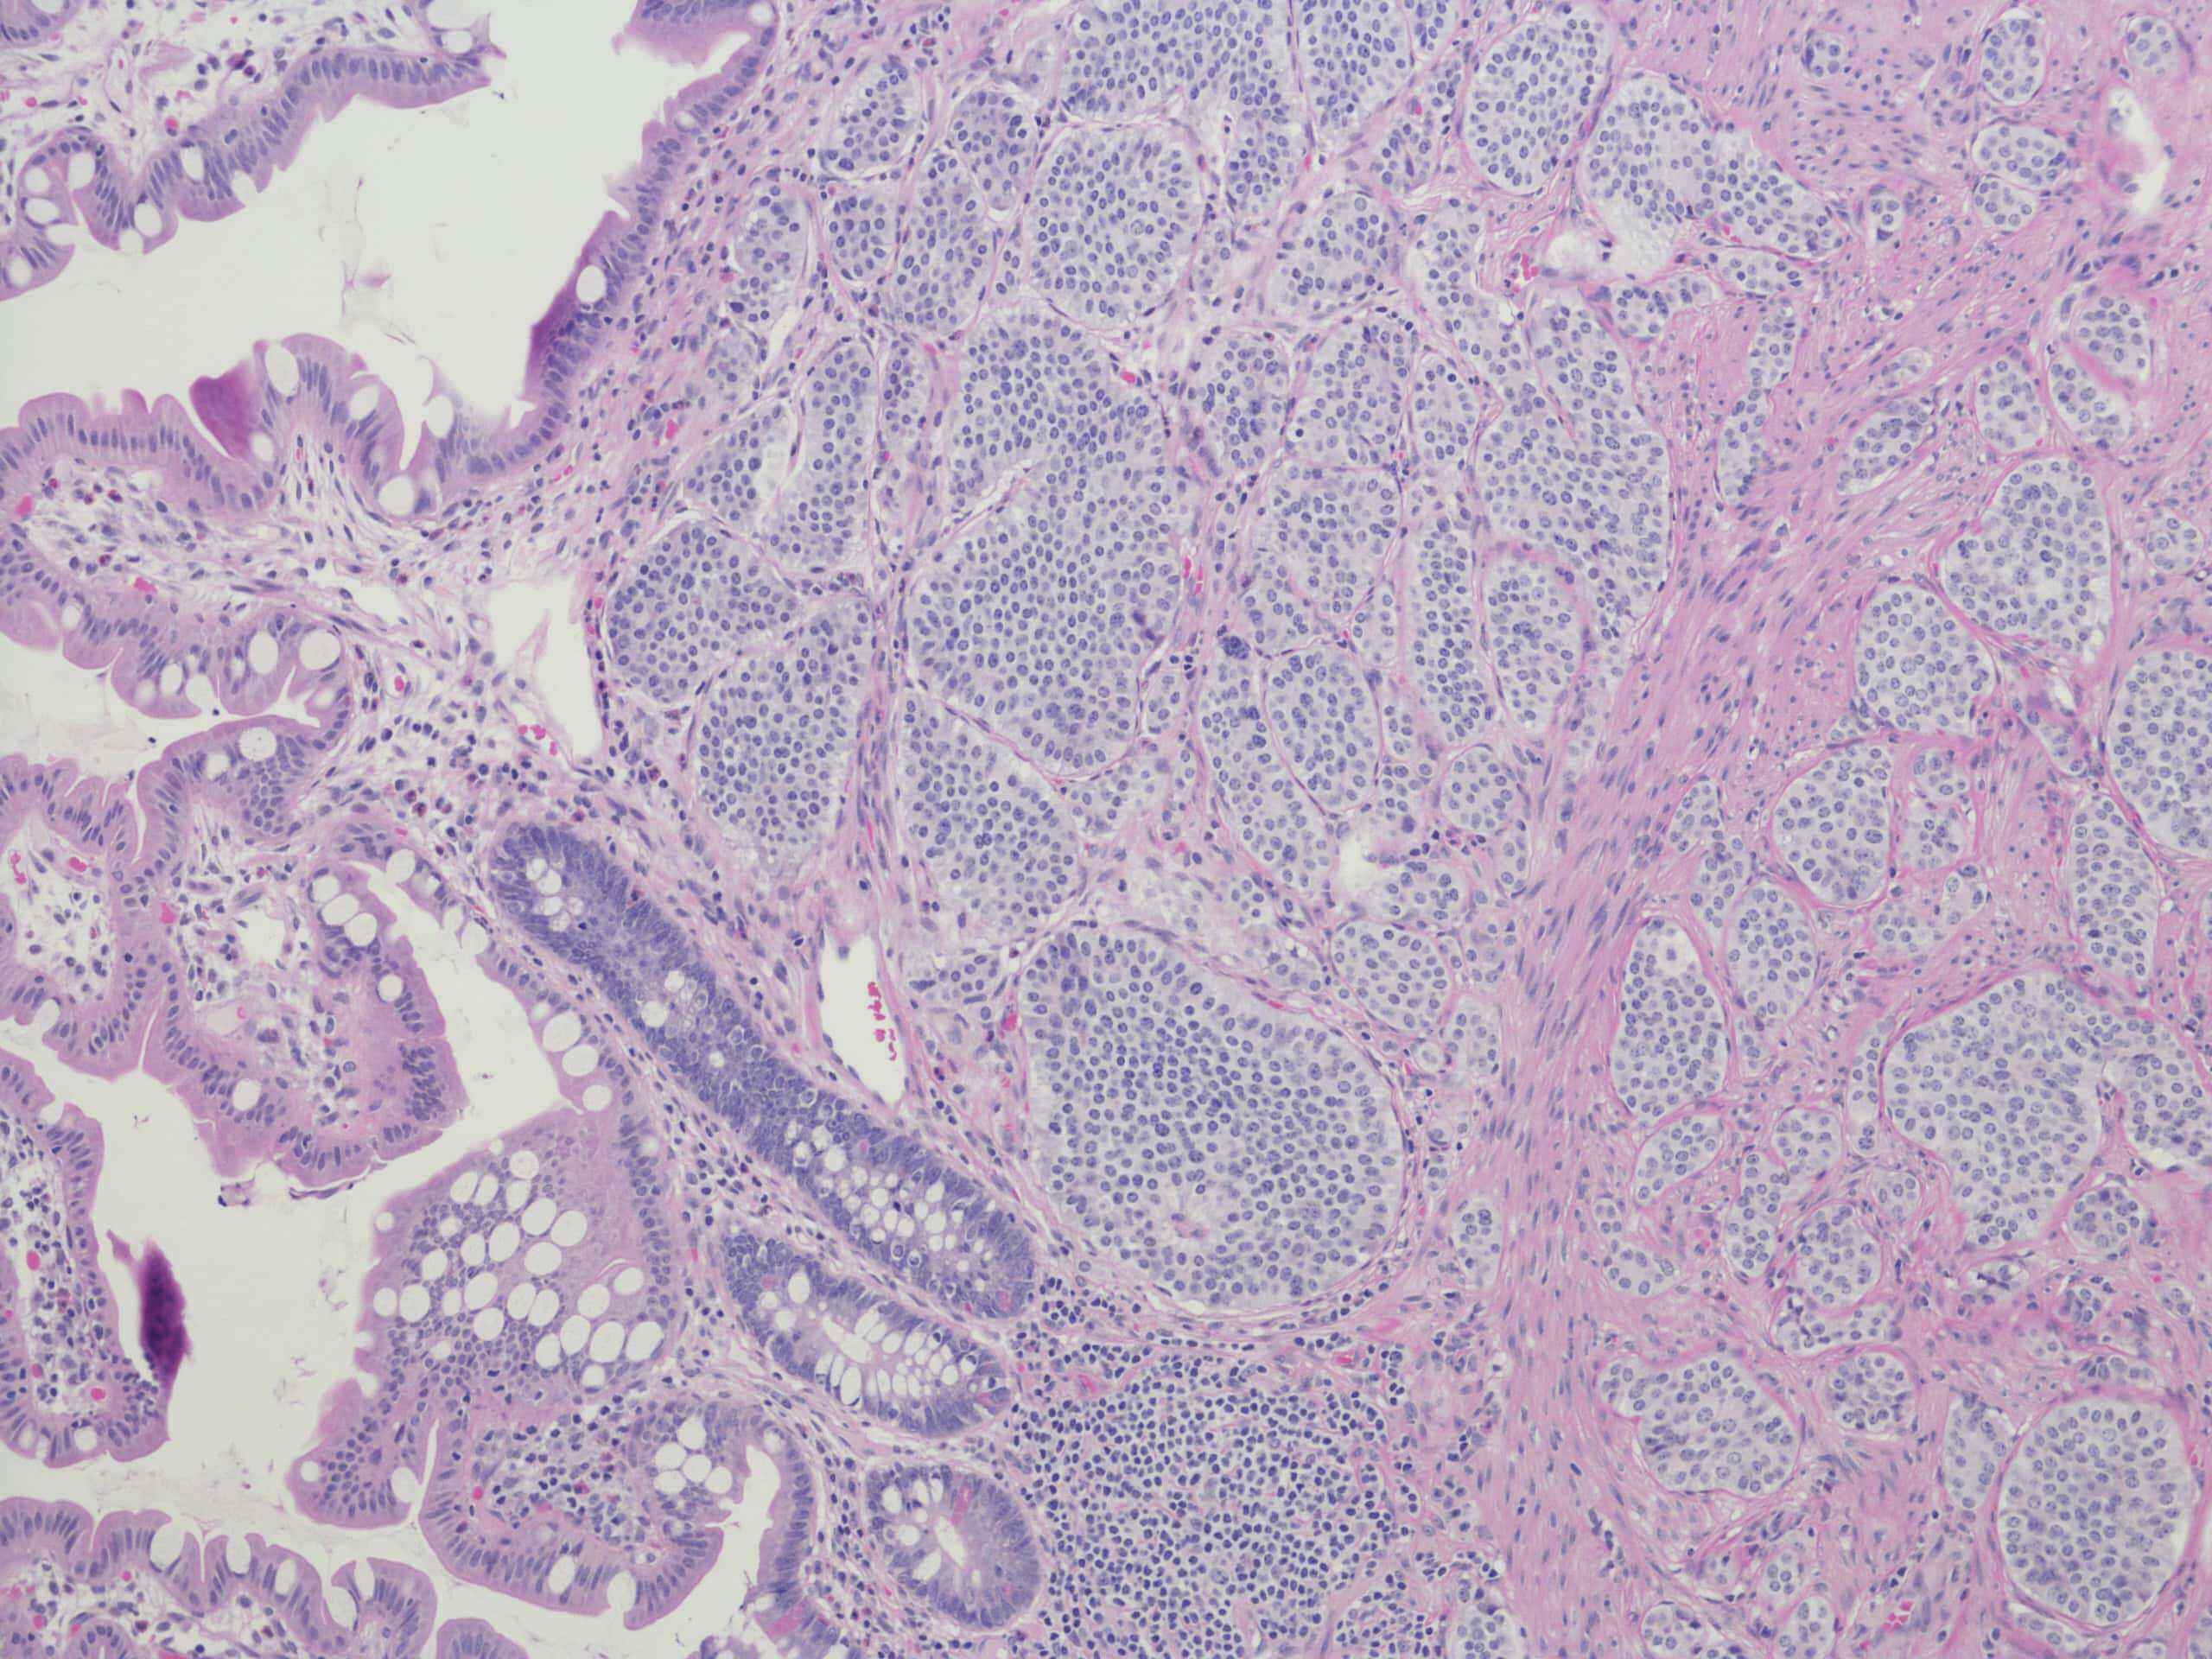

Microscopic view of tissue sample showing cellular structures and patterns, commonly used in medical imaging and pathology analysis

Neuroendocrine tumours are a diverse group of relatively rare cancers, with a reported incidence of 9 cases per 100,000 people in 2015.